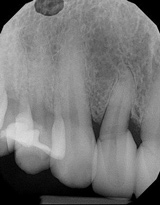

(2.) Pretreatment radiograph of tooth No. 7 showing widened periodontal ligament, dens in dente, dilacerations, and angular bone loss.

Figure 2

A 45-year-old female patient was referred to our office for the treatment of bleeding gums and sensitivity associated with tooth No. 7. Clinical and radiographic evaluations revealed highly inflamed tissues, easily provoked bleeding, and edematous palatal gingival tissue supporting tooth No. 7 (Figure 1 and Figure 2). Crowding, a widened periodontal ligament, dens in dente, deep probing depths, bleeding on probing, dilacerations, missing papilla, and angular bone loss were also observed, indicating that tooth No. 7 had a poor prognosis. The groove began at the cingulum and formed a deep fold of enamel that extended to the coronal third of the root. This radicular groove disrupted normal periodontal attachment and caused a self-sustaining, progressive localized periodontal pocket to form. The groove also presented a potential pathway for bacterial penetration into deeper parts of the root, which could lead to endodontic involvement if left untreated.6